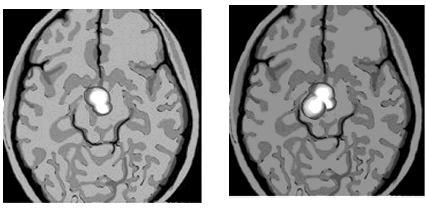

ქვემოთ მოცემულ ფოტოზე თქვენ ხედავთ ადამიანის ტვინის სკანირების შედეგს.

მარცხენა ფოტოზე ნაჩვენებია შეყვარებული ადამიანის ტვინი, მარცხნივ კი კოკაინის ზემოქმედების ქვეშ მყოფი ადამიანის ტვინი. შეუიარაღებელი თვალითაც კი მიხვდებით, რომ სურათი იდენტურია. ასე რომ, შეყვარებული ხართ თუ ნარკოტიკების ზემოდმედების ქვეშ, თქვენი ტვინისთვის ეს ერთი და იგივეა. (პირველს გირჩევთ). სკანირების შედეგად გაირკვა ასევე, რომ დედები, თავიანთი ჩვილის დანახვისას იგივეს გრძნობენ, რასაც შეყვარებული ადამიანი გრძნობს, ანუ ტვინის ის სფეროები აქტიურდებიან, რაც საყვარელი ადამიანის დანახვისას აქტიურდება.